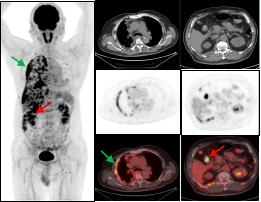

男,56岁,CEA: 40.5ng/ml,图A:肝脏多发转移瘤(红色箭头),图B:显示结肠肝曲高代谢肿块(绿色箭头),经肠镜证实为结肠腺癌。

右肺下叶肺癌伴阻塞性肺炎患者,CT难以精准指导穿刺,而PET/CT可准确区分肿瘤组织及炎性病变。绿色箭头示炎性组织,红色箭头示高代谢区域为肿瘤组织。

鼻咽癌全身转移:PET/CT显像示鼻咽左侧高代谢软组织肿块(绿色箭头);病理证实鼻咽非角化上皮癌,双侧颈部、肝脏及双侧髂骨多发转移瘤(红色箭头)。

胰腺癌全身转移:胰腺体尾部胰腺癌(绿色箭头),肝脏多发转移瘤及胸9椎体转移瘤(红色箭头)。

双癌检出:通过PET/CT一站式检查,同时检出两种肿瘤:甲状腺癌(绿色箭头)及子宫内膜癌(红色箭头),有利于临床治疗方案选择。

图A绿色箭头示右侧胸膜多发转移,图B红色箭头示结肠肝曲局部管壁稍厚形成软组织灶,糖代谢增高,肠镜证实结肠肝曲腺癌。